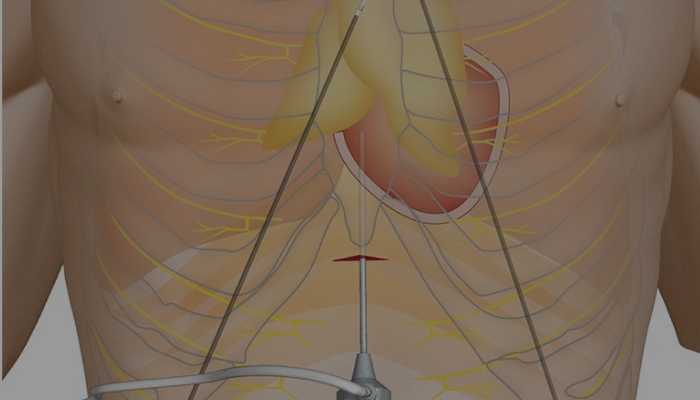

Robotic/ Thoracoscopic Surgery for Myasthenia Gravis

Myasthenia gravis surgery, often a thymectomy, involves removing the thymus gland to improve symptoms or manage the autoimmune condition.

Robotic/ Thoracoscopic Surgery for Myasthenia Gravis

Myasthenia gravis surgery, often a thymectomy, involves removing the thymus gland to improve symptoms or manage the autoimmune condition.